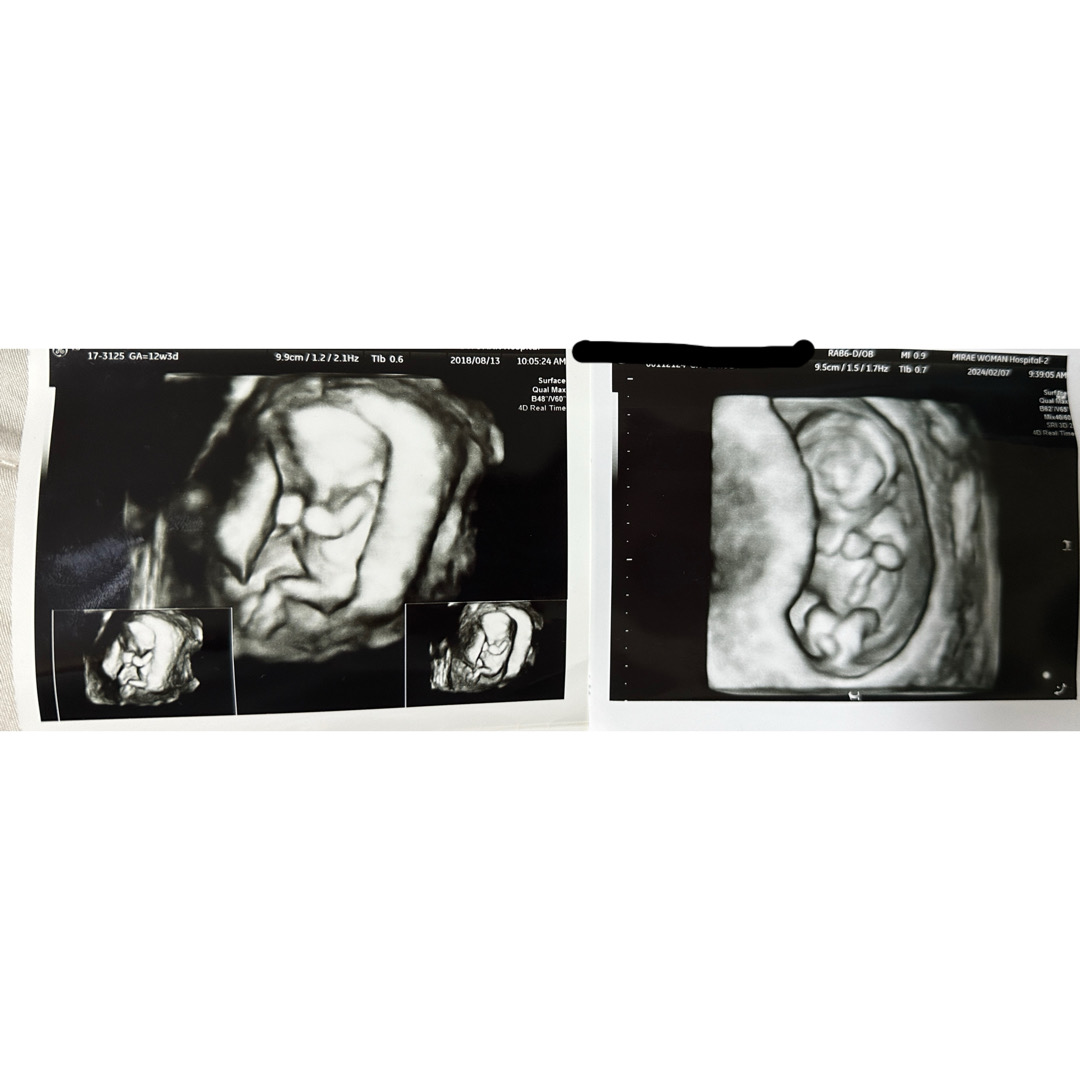

첫째둘째1차 입체춈파 똑같아요 ㅎㅎㅎ

어떻게 이렇게 똑같은지 ㅋㅋㅋ 두손모은 모습이며 크기도 비슷하구 귀여워요^^ 과연 성별도 같을지 궁금해 졌어요ㅎ 둘째는 입덧지옥이라 명절 연휴 잘 먹고 잘지내고자 입덧약도 처방받았어요. 그리구 여담? 으로 전 춈파 보기전까지 심장 떨려요ㅜㅜ 심장 안뛰면 어쩌지? 심장 잘 뛰고 있겠지?? 하며 긴장하는건 둘째라서 그런거 같아요ㅜ 첫째땐 무지하기도 했고 뱃속에서 무조건 잘 있다고만 생각했거든요.